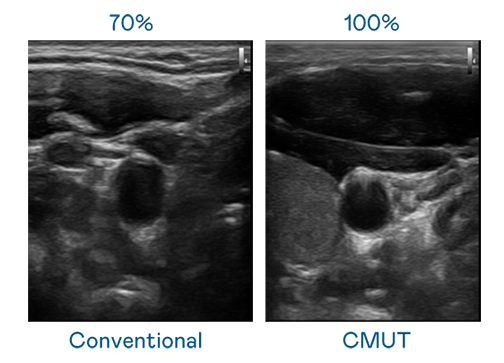

CMUT 技术是一种用电容式微机电元件来产生超音波讯号的技术。与传统 PZT 压电式技术相比,CMUT 频宽增加 30%,更宽频的超音波讯号让影像解析度大幅提升,是实现高影像品质医疗超音波扫描、促进精准医疗发展的关键技术。

超音波影像的解析度高低,首先取决于探头能发出的讯号频宽。CQ9电子 CMUT 可提供高清晰的超音波讯号,提供高频宽、高灵敏度、影像纹理细节更高的超音波影像,协助医护人员缩短影像判读时间及利用精准的医疗影像进行诊断。